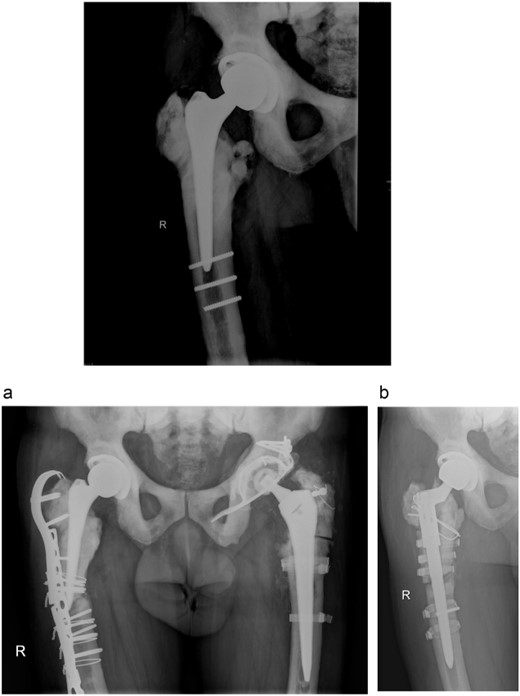

In 2008, the patient complained about increasing pain in the left hip. Laboratory tests were normal and X-ray imaging showed a loose cup which was replaced with a reinforcement ring and a cemented cup and the loose femoral component which was exchanged with a cementless revision stem (Fig. 2). Routine intraoperative tissue samples were positive and Staphylococcus epidermidis was isolated. A 3-month antibiotic treatment consisted of ciprofloxacin and rifampicin successfully cured the infection.

Anteroposterior radiograph of the left hip after revision surgery in 2008.